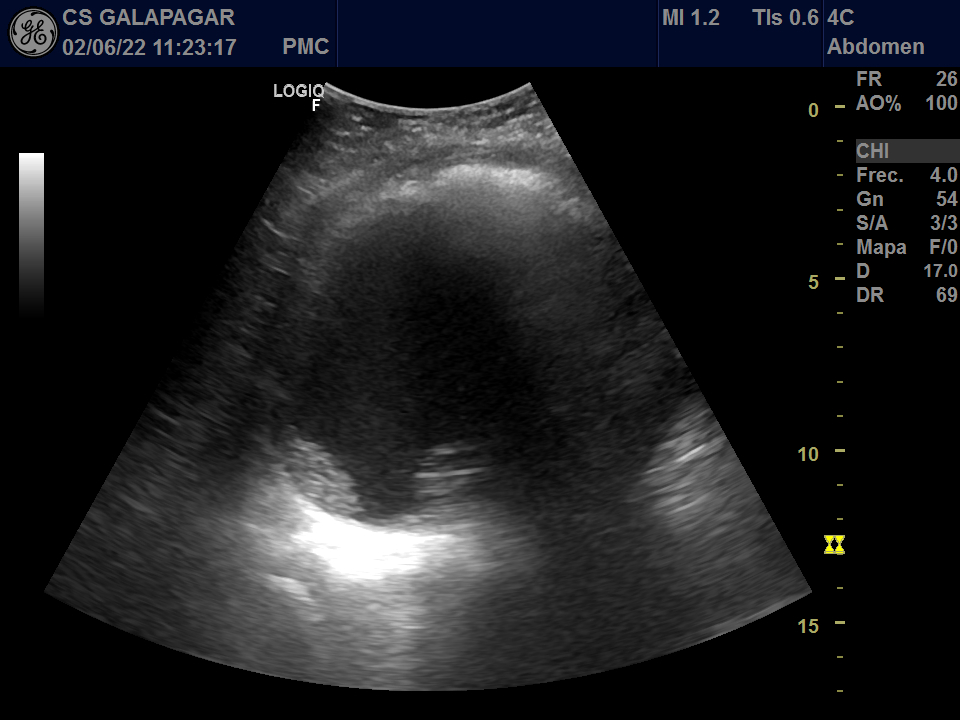

Eco de aparato urinario urgente donde se objetivaron múltiples lesiones excrecentes y plantearon tumor vs origen inflamatorio por la ausencia de vascularización. Eco TV: quiste sin Doppler. En la exploración vaginal: se palpó masa que llega 10 cm por encima de pubis y abomba cara anterior de la vagina. TAC abdomino-pélvico: lesión quística pélvica con aislados polos sólidos excéntricos. La lesión produce efecto masa sobre estructuras adyacentes. Se realizó laparatomía exploratoria con toma de biopsias.

JC en centro de salud: pólipo intravesical vs quiste intravesical vs tumoración vesical. En el hospital el diagnóstico diferencial inicial fue tumor vs origen inflamatorio. Diagnóstico final anatomopatologico carcinoma de células claras de ovario izquierdo.